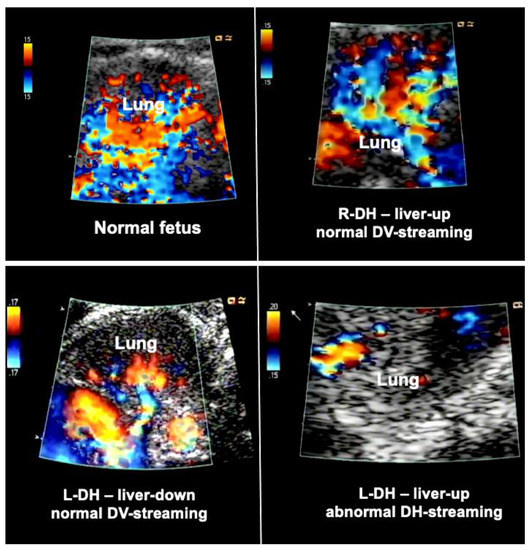

In order to overcome this limitation, additional hemodynamic studies of fetuses with diaphragmatic hernia—with a particular focus on fetal left–right-heart-symmetry—can be performed, such as assessment of ductus venosus streaming and lung blood flow monitoring [41,42,43]. Using these parameters, I have observed that most fetuses with liver-down left diaphragmatic hernia exhibit normal streaming of ductus venosus blood into the left side of the heart of the fetus. As a result, both sides of the heart are of equal size, pulmonary blood flow signals are easily visualized, and pulmonary vasodilation in response to diagnostic maternal hyperoxygenation can be produced (Figure 3). Taken together, these findings point to a milder postnatal treatment course and herald a better prognosis.

Figure 3.

Examples of lung blood flows of a normal fetus (top left) and fetuses with diaphragmatic hernia during diagnostic materno–fetal hyperoxygenation. Most fetuses with liver-down left diaphragmatic hernia (L-DH) exhibit normal streaming of ductus venosus blood into the left side of the heart (bottom left). As a result, both sides of the heart are of equal size, pulmonary blood flow signals are easily visualized, and pulmonary vasodilation in response to diagnostic maternal hyperoxygenation can be produced. In contrast, most fetuses with liver-up L-DH exhibit preferential streaming of ductus venosus blood into the right side of the heart of the fetus. As a result, there is less preload to the left side of the heart, which in turn becomes hypoplastic. In addition, pulmonary blood flow is often markedly decreased (bottom right). Fetuses with right diaphragmatic hernia (R-DH), despite liver herniation, present with normal ductus venosus streaming into the heart. Therefore, as a rule, in these fetuses, neither isolated left, nor isolated right heart hypoplasia are observed, and color Doppler signals of pulmonary blood flow are often normal (top right).

In contrast, most fetuses with liver-up left diaphragmatic hernia exhibit preferential streaming of ductus venosus blood into the right side of the heart of the fetus. As a result, there is less preload to the left side of the heart, which in turn becomes hypoplastic. Probably as a result of the oxygen-enriched ductus venous blood reaching the lungs, morphologic changes contributing to pulmonary hypertension can develop. During Doppler ultrasound studies, pulmonary blood flow signals are less pronounced and pulmonary vasodilation in response to materno–fetal hyperoxygenation is often markedly attenuated (Figure 3).

In contrast, fetuses with right diaphragmatic hernia—despite liver herniation—present with a more normal infracardiac spatial arrangement of venous vessels, and hence, normal distribution of ductus venosus blood within the fetal heart [43]. Therefore, as a rule, in these fetuses, neither isolated left, nor isolated right heart hypoplasia are observed (I have encountered only one exception) (Figure 3). Nevertheless, there may be symmetrical underdevelopment of both, left and right cardiovascular structures, from compression by the herniated organs. Yet even in severe cases, a close to normal degree of blood flow can be observed within the left lung (Figure 3). In ECMO centers such as ours, this hemodynamic advantage seems to contribute to survival rates of more than 80% for this condition [34].